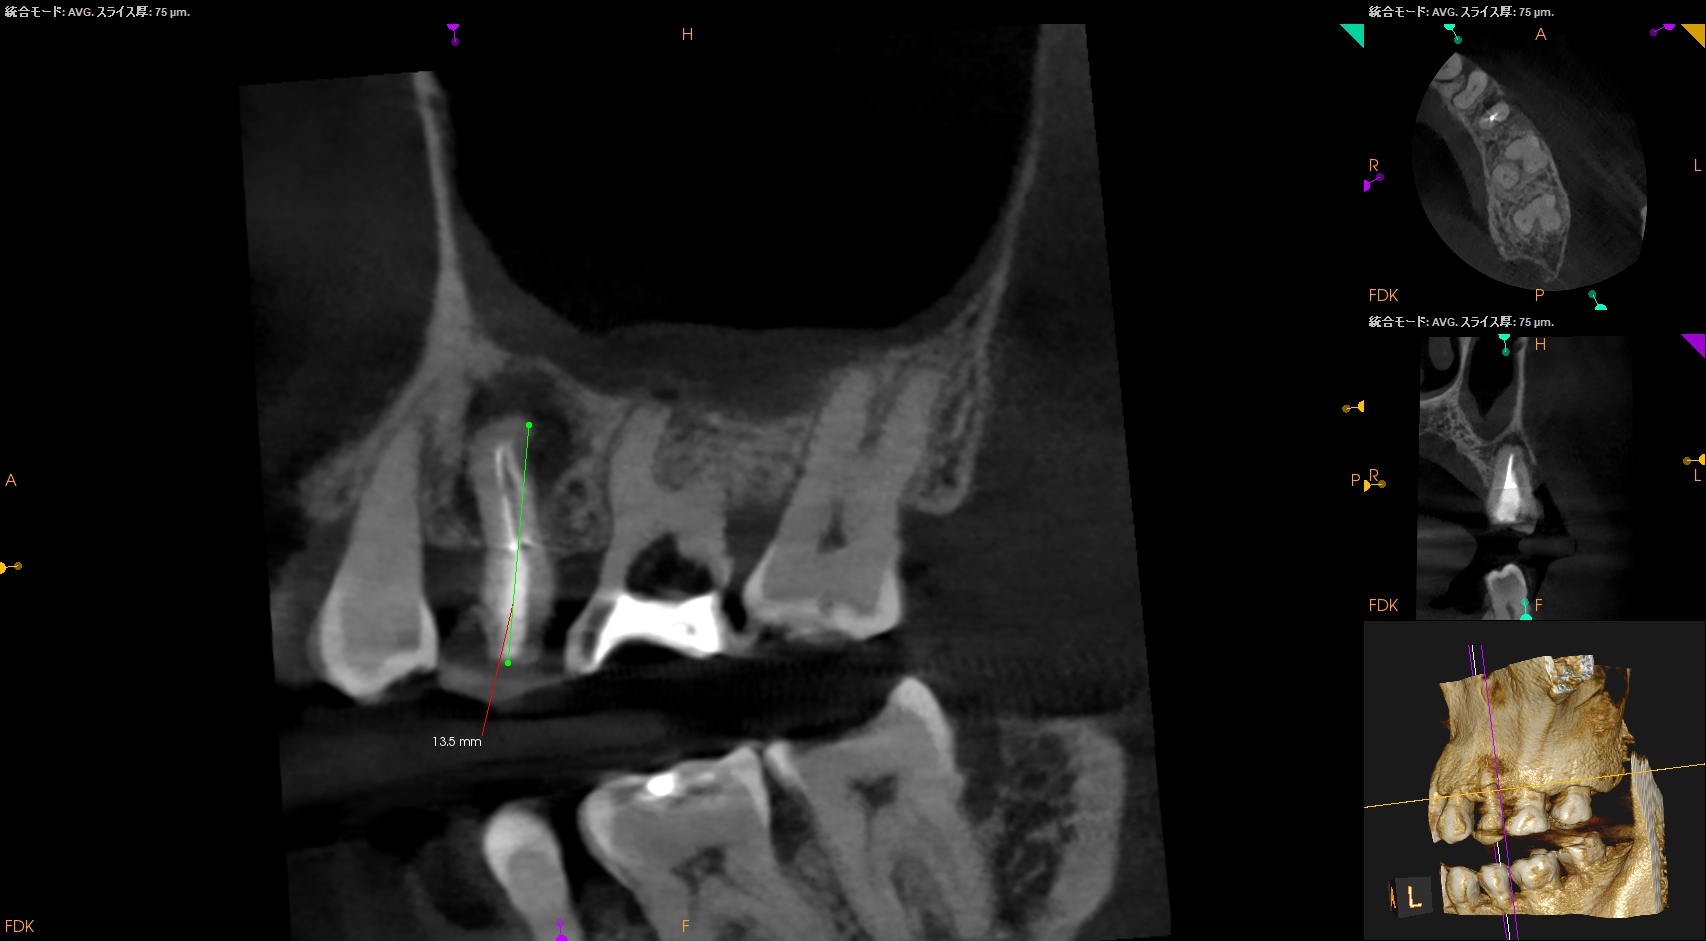

CBCTも撮影した。

これはマストの医療行為である、と私からは告げておこう。

おおよその作業長が類推できる。

が、いずれにしてもこの治療での最大のポイントになるのはMB2がどこにあるか?である。

MB2の根尖部にはCBCTで根尖病変があるからだ。

作業長が術前に予測したCBCTでの作業長に近似していること

を。

これが、

CBCTの威力

である。

ということで、術後にPA, CBCTを撮影した。

#14

MB1

MB2

DB

P